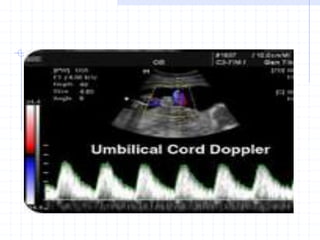

Umbilical Doppler Velocimetry

Indication:

IUGR

PET

D.M.

Any high risk pregnancy

Use a free loop of umbilical cord to

Umbilical Artery Doppler

Umbilical cord doppler